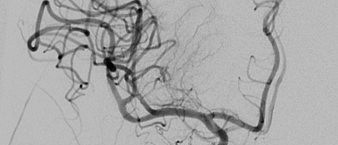

Mit Hilfe der Digitalen Subtraktionsangiographie (DSA) werden die Arterien über einen Katheter, der über die Leistenschlagader eingebracht wird und bis in die Halsgefäße navigiert mit  jodhaltigem Kontrastmittel sichtbar gemacht. Die Angiographieanlage macht dabei eine Röntgenleeraufnahme vom Kopf. Das bedeutet, alles „Störende“ (Knochen und Gehirnmasse) wird subtrahiert und nur die Gefäße bleiben sichtbar.

Bei der Thrombektomie nutzen die Neuroradiologen dieses Verfahren, um Bilder der Arterien im Kopf in Echtzeit auf einen großen Bildschirm zu übertagen. Mit Hilfe noch kleinerer Katheter und Drähte können kleinste Blutgefäße im Kopf erreicht werden und das hier befindliche Blutgerinnsel mit einem Katheter entfernt werden. Wie auf einer „Autobahn“ fahren die Neuroradiologen dann mit einem Katheter die Hauptschlagader entlang am Herz vorbei, zu der gewünschten „Ausfahrt“, demmit dem Thrombus verschlossenem Gefäß. Besonders schön ist es zu sehen, wenn die Patienten am Tag nach der Thrombektomie wieder zu Fuß zur Kontrolluntersuchung kommen können.